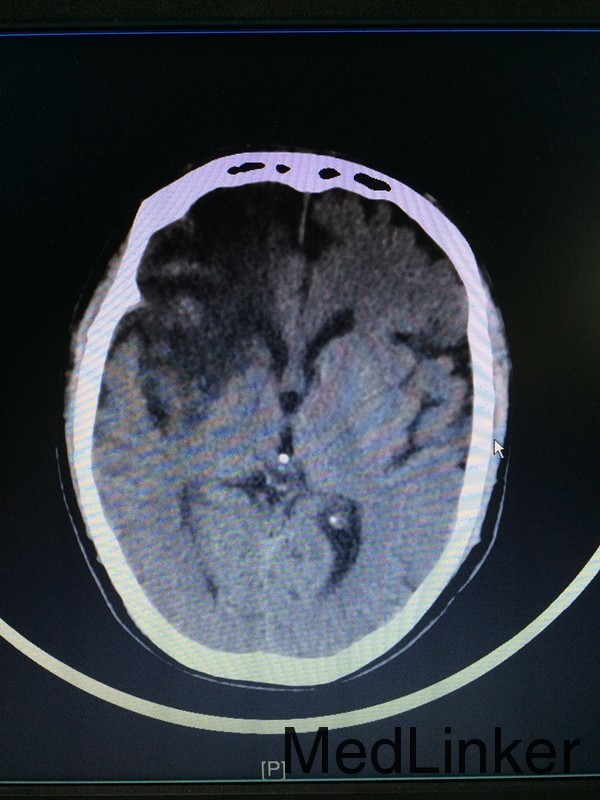

主诉:左侧肢体乏力28天 病史:患者60岁男性,于入院前28天无明显诱因出现左侧肢体乏力,伴言语不清,表现为行走不稳、神志模糊,较烦躁,无头痛、头晕、恶心呕吐等,于当地医院行头颅CT提示:大脑中动脉高密度影。患者第二天出现头痛伴呕吐,急查头颅CT提示:大面积脑梗。

查体:左侧上肢2级,下肢2级,右侧肢体肌力正常 辅助检查:查头颅CTA提示:右侧额叶及岛叶(包括基底节)脑梗塞,轻度脑萎缩,CTA未见明显异常

诊断:右侧额叶及岛叶大面积脑梗塞 治疗:予活血化瘀、改善血管痉挛、脱水降颅压等治疗,并申请康复、高压氧等治疗。